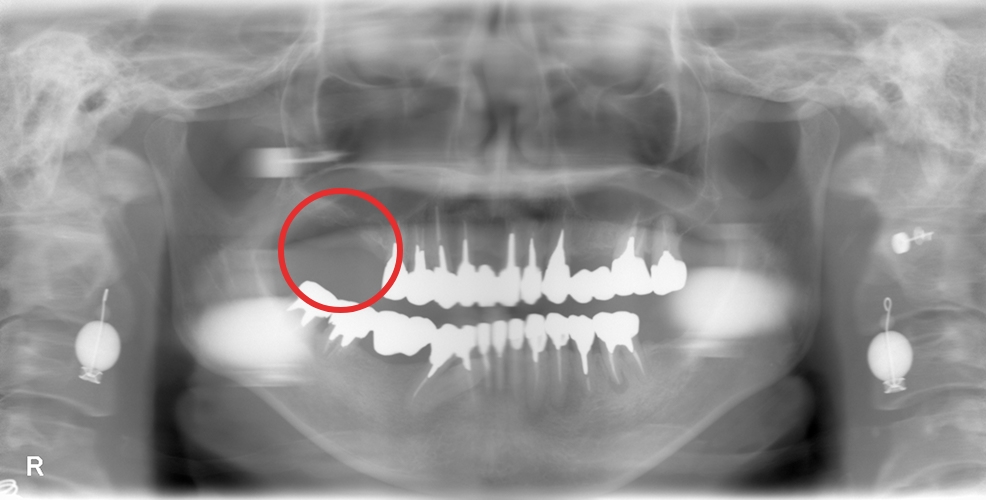

上部構造装着後のレントゲンと口腔内写真